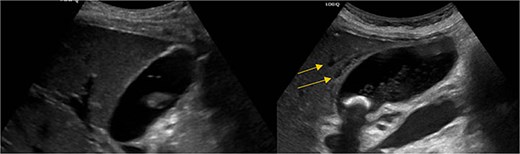

Computed tomography (CT) in the ER showed normal gastric bypass anatomy with moderate colonic stool burden. Negative for biliary pathology. Follow up ultrasound showed cholelithiasis without evidence of acute cholecystitis. A confirmatory HIDA showed normal filling of the gallbladder with rapid clearance into the small bowel and ejection fraction of 62% (Fig. 1).

HIDA scan showing normal gallbladder filling and rapid emptying of nucleotide contrast in the SB following administration of CCK.

Pericholecystic fluid (arrows) and positive sonographic murphy sign present on the post-HIDA ultrasound (right) that was not previously seen on the pre-HIDA ultrasound on admission (left).